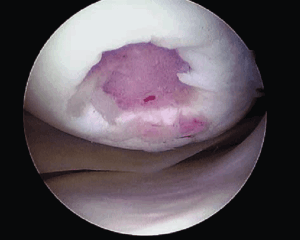

Локальное травматическое повреждение коленного сустава, вид через артроскоп.